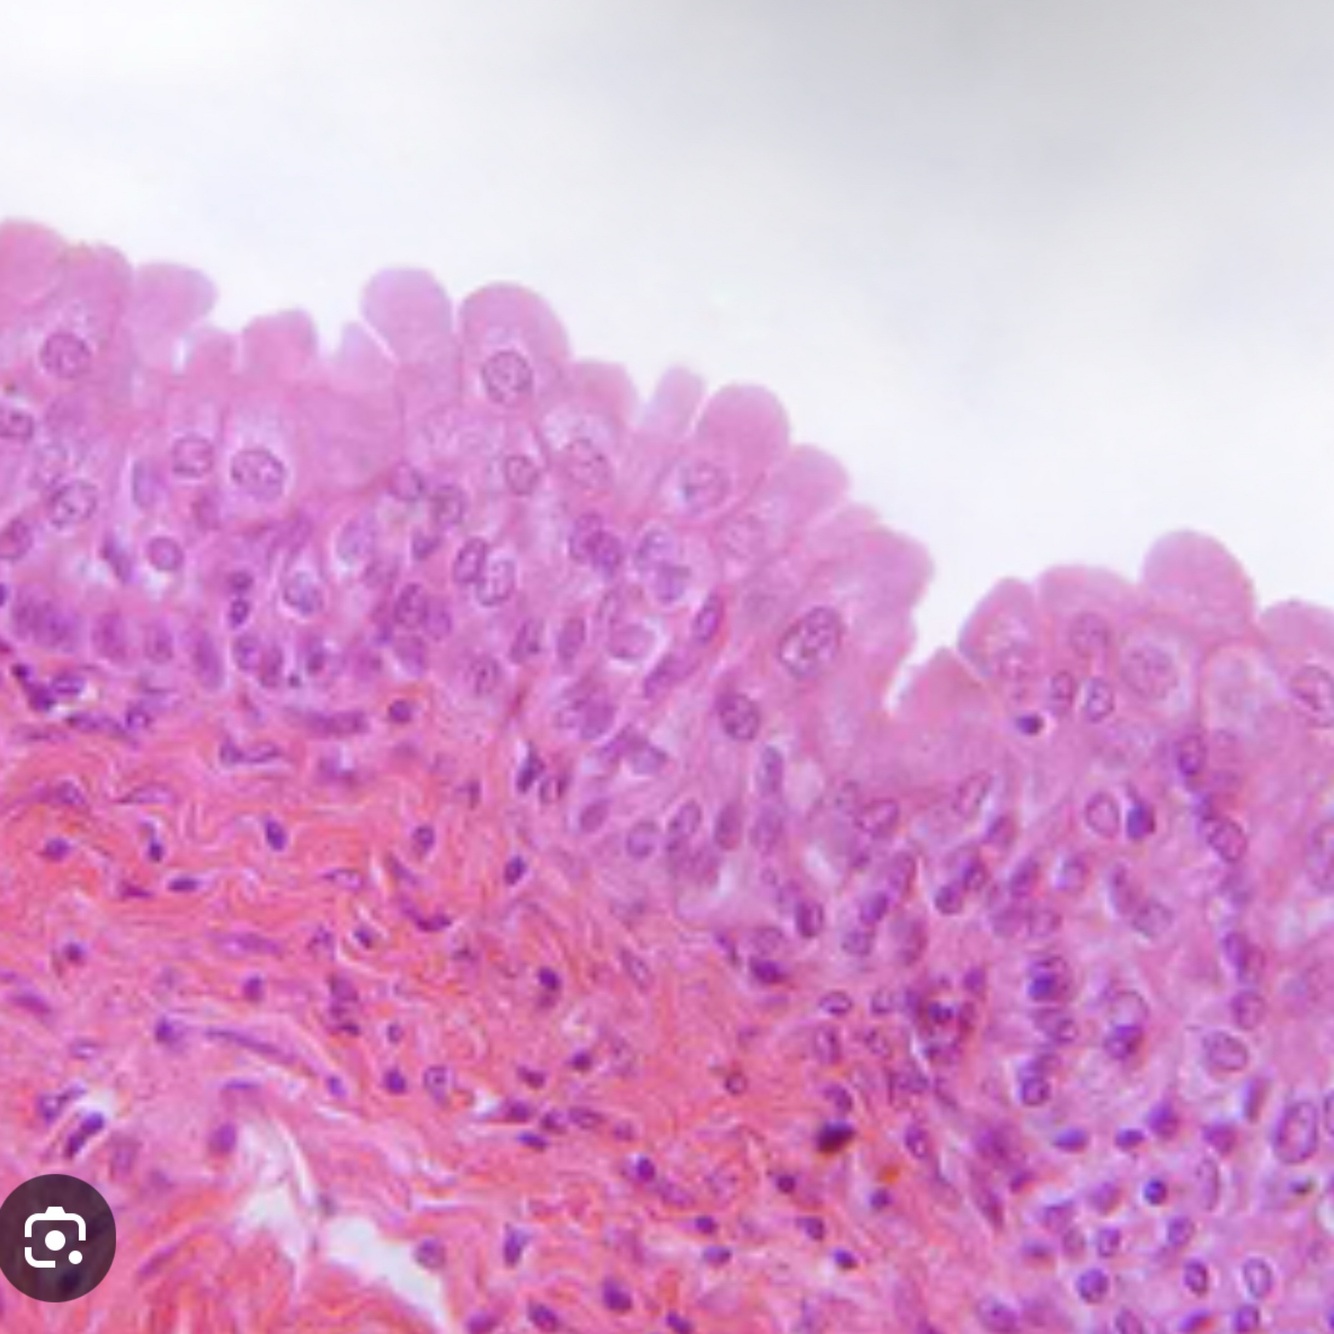

1. Transitional epithelium

2. Urinary tract

3. Stretch/ recoil